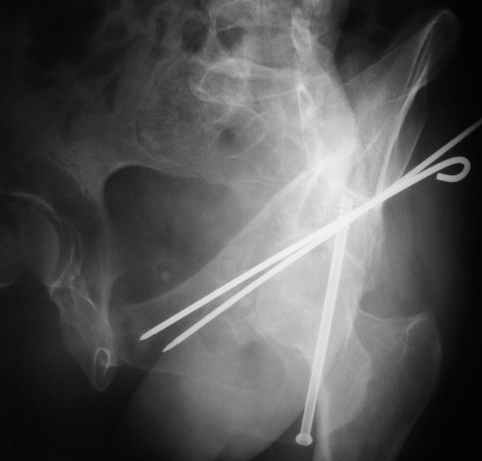

Однако есть альтернатива. Репозиция из подвздошного доступа тазовыми щипцами с разнодлинными браншами или тазовым пистолетом, а фиксация задней колонны через седалищный бугор или тазрвыми винтами 4,5 или каннюлированными 6,5 или 7,3. По-моему я посылал на ортофорум такой снимок, когда жаловался на ишемический неврит седалищного нерва через сутки после операции. Не забудь про шейку бедра - мне кажется будет хорош длинный PFN любой фирмы, какую ты найдешь, а нет так UFN + miss a nail, как это здорово делают мои земляки - Ебурбуки. Пока.

Откровенно говоря, репозиция оказалась очень непростым делом, несмотря на то, что при расширенном илео-феморальном доступе все переломы как на картинке.

Сначала пытался отрепонировать смещенную заднюю колонну, но ничего из этого не получалось пока не репонировал фрагмент крыла подвздошной кости, который клином входил между отломками тела илии и задней колонной дистанция-то всего каких-то 3-5 мм, но чтобы сложить этот puzzle пришлось попотеть, я уже и дистракционные щипцы и бедренный дистрактор крутил, в конце концов все состоялось, а передняя колонна уже саморепонировалась, мне оставалось только компрессирующие винты завинтить

> Однако есть альтернатива. Репозиция из подвздошного доступа тазовыми

> щипцами с разнодлинными браншами

Пробовал и разновеликими и равновеликими прямыми и изогнутыми тазовыми щипцами. По длине репозиция удается, но имеется остаточное ротационное смещение нижнего отдела вертлужной впадины кнаружи и его устранить было не просто, щипцы постоянно *соскальзывали*. ( как в анекдоте про поручика

Ржевского и процесс на фортепиано...:-))